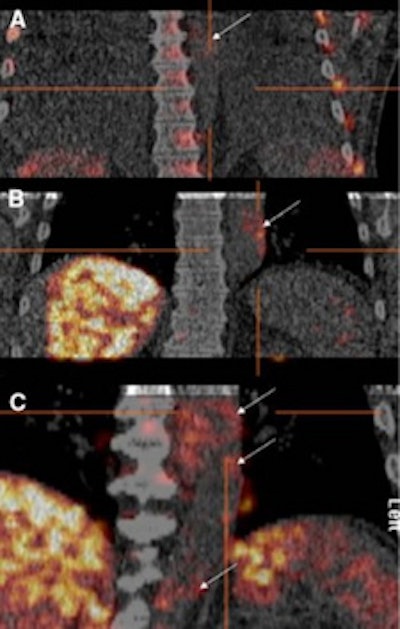

| The three images represent clinical myocardial FDG-PET/CT viability studies, which show Grade 0 or negative aortic FDG uptake (A), Grade 1 or mildly positive aortic FDG uptake (B), and Grade 2 or very positive aortic 18-FDG uptake (C). Images courtesy of the University of Ottawa Heart Institute. |

The researchers then evaluated the areas of FDG uptake and activity relative to blood pool. Grade 0 or negative evaluation was given to areas with no activity, or if the average SUV to blood pool average SUV ratio was less than 1.25. Grade 1 or mildly positive activity indicated a ratio of average SUV to blood pool average SUV of 1.25 to 1.50. Grade 2 or very positive activity indicated that the ratio of average SUV to blood pool average SUV was greater than 1.50.

The analysis found that six (17%) of the 30 studies had grade 2 or very positive FDG uptake, while 19 studies (63%) had grade 1 or mildly positive FDG uptake. The remaining five studies (17%) had little or no FDG uptake.